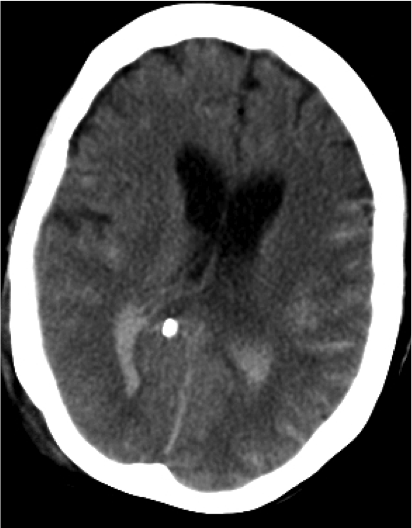

Hemorragia Intraventricular.

- La hemorragia intraventricular se origina por la rotura de las venas subependimarias a lo largo de la superficie de los ventrículos o por extesnión directa de una HSA o de un hematoma parenquimatoso al sistema ventricular.

- Puede ocasionar hidrocefalia.